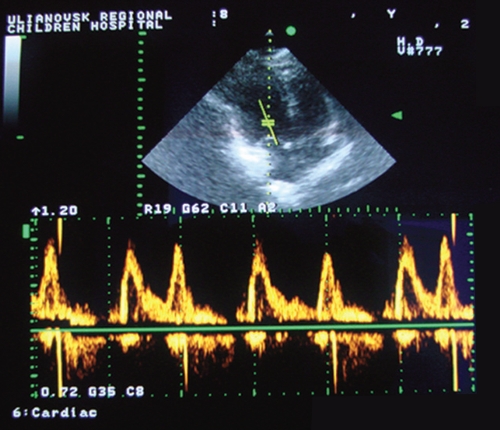

Далеко не всегда, человеку, у которого выявили снижение диастолической функции левого желудочка, в конечном счете, ставят диагноз сердечная недостаточность хронического типа, поскольку для этого необходимо также наличие других характерных признаков, а также небольшое снижение показателей фракции выброса. Решение о постановке диагноза принимается доктором после тщательного исследования работоспособности всех частей миокарда, а также на основе результатов диагностических процедур.